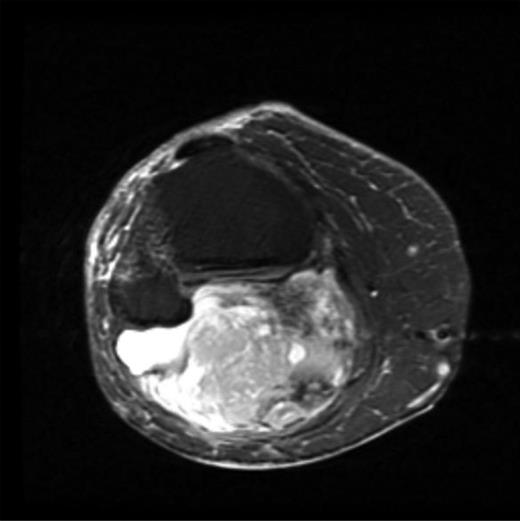

The MRI scan of the right knee (Figs 2 and 3) with gadolinium-enhancement showed a large mass lesion in the posterior aspect of the right knee extending into the popliteal fossa and into the upper third of the right leg having appearance of bursal pathology. Post gadolinium images showed evidence of circumferential rim enhancement but no internal enhancement indicating the presence of a fluid filled lesion. The mass (Figs 4 and 5) measured ∼8.39 × 6.14 × 12.72 cm and was seen between semimembranosus and biceps femoris muscles. There was no evidence of any infiltration of either the sciatic nerve or the popliteal vessels. A likely diagnosis of complicated synovial cyst with a differential diagnosis of haematoma was reported and a provisional diagnosis of Baker's cyst was established.

T1-weighted MRI image showing mass occupying whole of posterior aspect of knee extending to proximal portion of the leg.